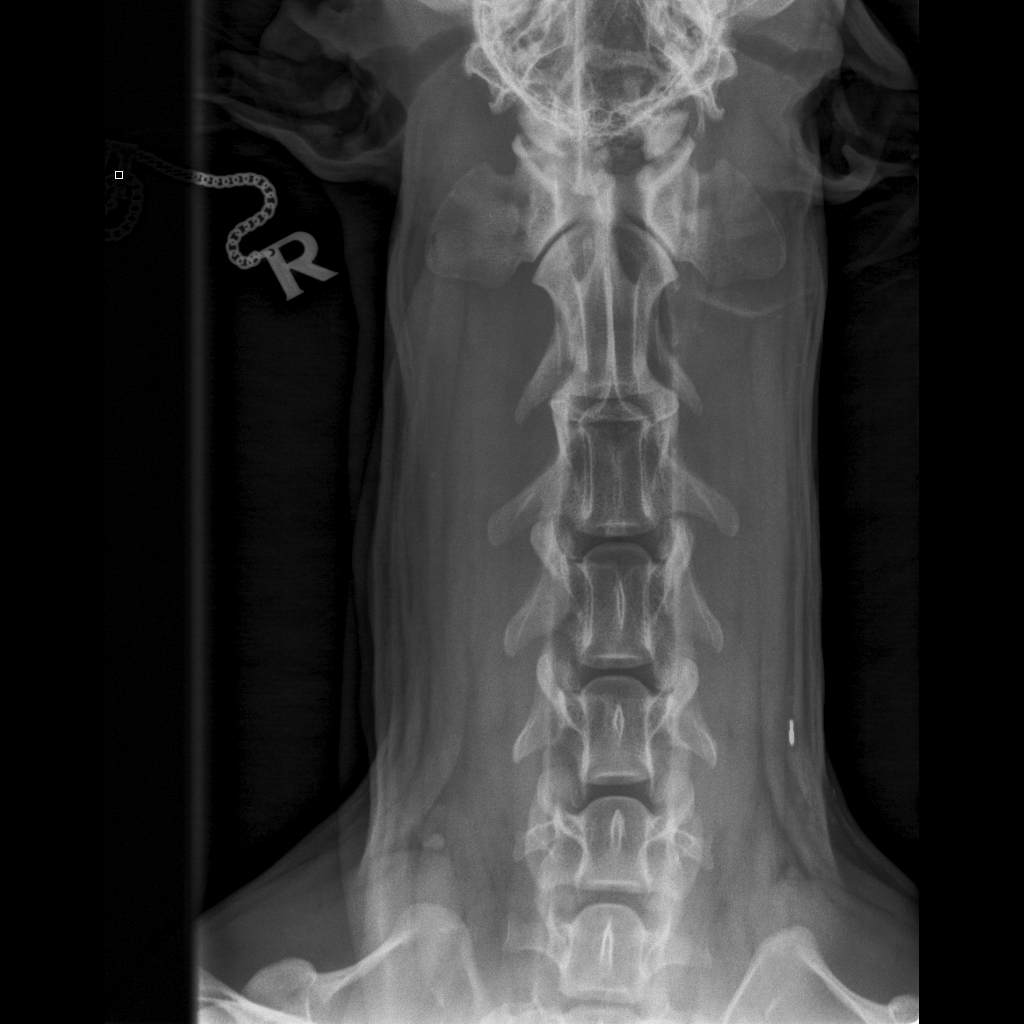

Koko selkä kuvattu terveeksi toistamiseen 1.9.14:

kaularanka

rintaranka

lanneranka

* * * *

Niskasta otettu taivutuskuvat 17.10.14:

kaularanka1

kaularanka2

kaularanka3

Quti viety lääkäriin, koska vingahtelee kääntäessän päätään. Koko selkä kuvattiin, ei muutoksia. Oireiden jatkuessa kaularanka

magneettikuvattiin. Kuvanneen eläinlääkärin mielestä Nomilla on välilevyrappeuma ja kaikki harrastaminen mietittävä uudelleen.

Halusimme toisen mielipiteen Timo Talviolta, joka halusi ottaa Nomin kaularangasta taivutuskuvat. Talvion mukaan kyseessä ei ole

välilevyrappeuma vaan taivutuskuvissa näkyy kaularangan nikamien 5 ja 6 välillä liukuma. Lääkekuurin ja levon jälkeen voi

harrastamista jatkaa normaalisti. Talvion lausunto:"Kyse on nikamien välisestä "löysyydestä". Selkärangan rakenteelliset

viat ovat pääsäänöisesti perinnöllisiä, mutta tällainen lievä nikamien välinen liikkuvuus ei sellaisenaan ole perinnöllistä,

toki perintötekijät voivat altistaa tämänkaltaisen tilan kehittymiseen."